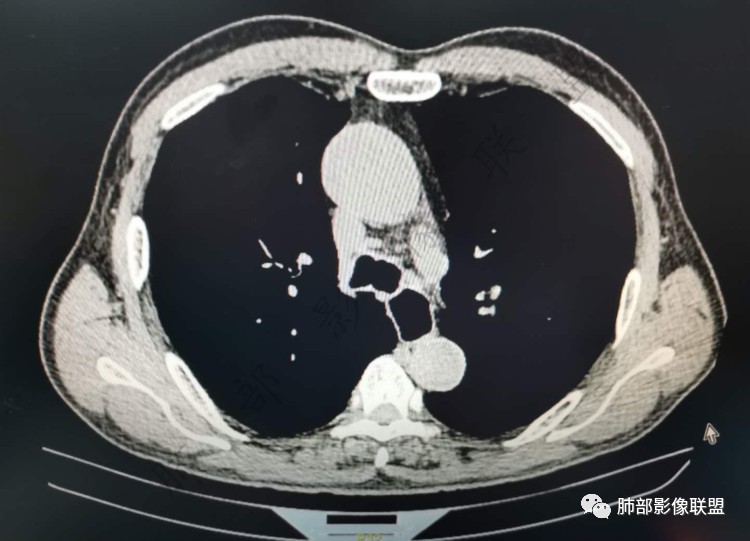

老年男性,炎性指标略高,肺气肿背景。右肺上叶胸膜下结节,部分边缘平直,部分稍膨隆,供血血管增粗,增强扫描病灶中心密度减低,呈环形强化,邻近脂肪间隙清晰。考虑炎性肉芽肿或慢性炎症,鉴别鳞癌。

右肺上叶前段胸膜下结节,边缘分叶毛刺,血管集束,支气管截断,纵膈胸膜牵拉,内乳动脉增粗,密度不均,中央可见坏死,两个月短期随访结节有增大,考虑恶性,腺癌。鉴别结核。

老年男性,炎性指标略高。影像表现右肺上叶胸膜下结节,膨胀性生长部分边缘平直,边界清晰,病灶可见血管集束征,近段支气管阻断?增强扫描病灶中心密度减低,低密度区边界模糊,外围环形强化。老年性,不能排除恶性病变,周围性鳞癌,其次才考虑炎性肉芽肿或慢性炎症

右肺上叶前段胸膜下结节,近段支气管截断,血管伸入结节内,密度不均,同侧临近内乳动脉增粗,不均匀强化,肺气肿背景,两月明显增大,考虑低分化鳞癌,隐球菌代排

老年男性,白细胞计数及CRP稍高,右肺上叶结节,两个月来有增大,部分边缘可见边界模糊的GGO,局部边缘平直、凹陷,临近胸膜增厚,内见坏死,坏死区边界未见明显壁结节,壁较厚而且均匀强化,支气管似乎有扩张然后截断,近端血管增粗明显。考虑炎性病变,脓肿?有结核病人密切接触史,注意是否为结核。有点难以理解的是为什么右侧内乳动脉增粗明显。

老年男性,无症状,炎性指标增高。肺气肿背景,右肺上叶前段结节,边缘部分平直部分澎隆,血管集束,支气管至病变边缘似截断,近端扩张。增强环形强化,中心坏死。两月内病灶增长太快,考虑炎性肉芽肿,慢性脓肿?结核?癌待排。

内乳动脉关系似乎不密切

内部有低强化区,边界尚清